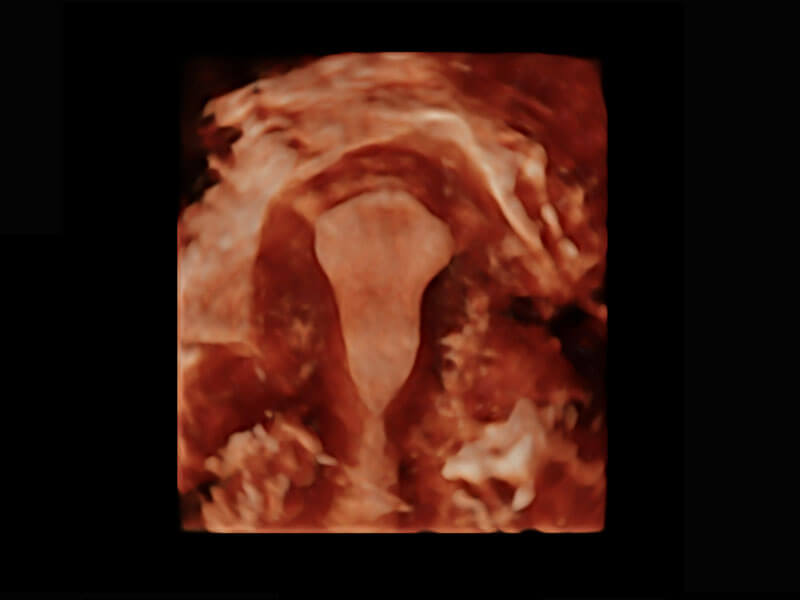

P60优异的图像质量搭载专科探头,在妇科基础疾病的诊断、卵泡生长的监测、输卵管通畅情况的判别等方面为您提供生殖应用方案。

腔内三维-宫内节育器